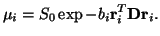

The diffusion tensor has often been used to model local diffusion

within a voxel (e.g. [10,15,16]). The

assumption made is that local diffusion may be characterized with a 3

Dimensional Gaussian distribution ([10]), whose covariance

matrix is proportional to the diffusion tensor,  . The

resulting diffusion weighted signal,

. The

resulting diffusion weighted signal,  along a gradient direction

along a gradient direction

, with

, with  -value

-value  is modeled as:

is modeled as:

where  is the signal with no diffusion gradients applied.

is the signal with no diffusion gradients applied.  ,